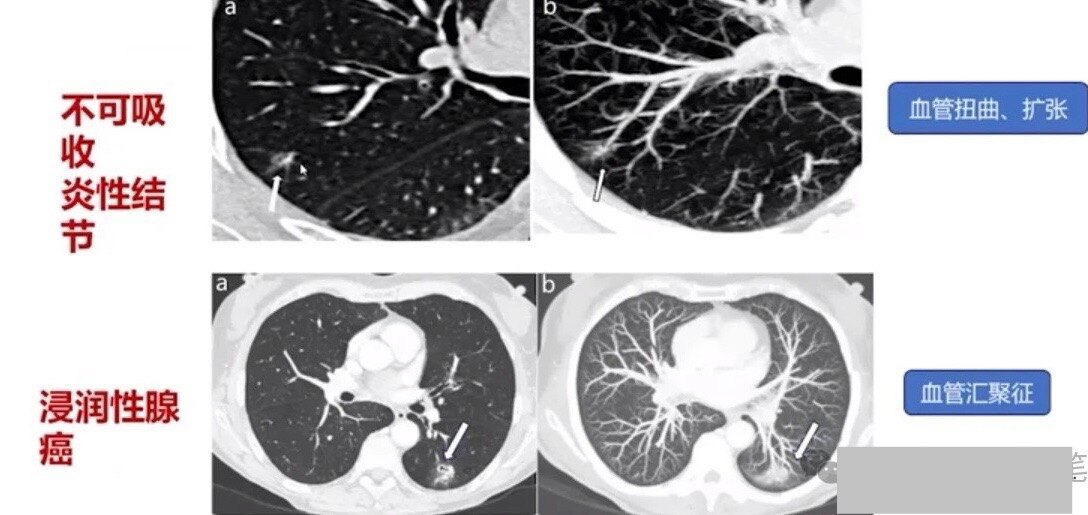

为何不吸烟女性发病率越来越高?磨玻璃结节是什么?关注肺癌防治他被确诊为右肺小细胞癌晚期。据了解,患者确诊前,家人以为只是普通感冒。重庆市璧山区中医院肿瘤科主任莫浩:肺部的肿瘤,症状是以咳嗽为... 胸外一科主任医师马少华:所谓的磨玻璃结节是影像学诊断名词,肺癌是个病理学诊断名词,它完全是两回事,2毫米以上的结节都能在CT上发现,实...

10岁女孩,确诊肺癌!让医生发现了她右肺下叶有一纯磨玻璃结节,医生给出的诊断结果也是良性结节、炎症。 圆圆的父母对这个所谓的“结节”很重视,... 微浸润腺癌大小约0.7厘米,紧邻胸膜。”因为是早期的微浸润性腺癌,术后无需放化疗。术后3天,圆圆顺利出院。之后,她只需定期复查即可...

年轻女孩干咳一周确诊肺癌!再三提醒:出现这4个症状一定要小心胸部CT的检查结果是:右肺上叶有个接近5厘米的肺结节。而且,医生判断这个结节很可能不是单纯的“肺结节”,大概率是肺部恶性肿瘤。赶紧... 复查中结节有增大或实性成分增多,最好通过相关诊治手段协助明确或者手术切除出现这4个症状,一定要小心肺癌肺癌仍是我国第一大癌。说到...